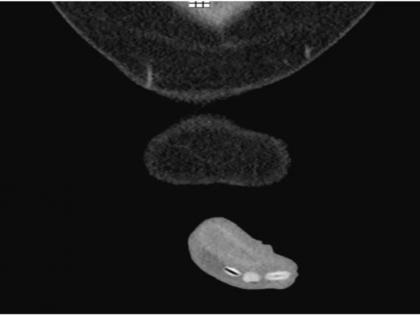

मिशिगनच्या स्पॅरो हॉस्पिटलमध्ये या तरुणाला गंभीर अवस्थेत भरती करण्यात आले होते. तो वेदनेने विव्हळत होता. तसेच लघवीही करू शकत नव्हता. डॉक्टरांनी जेव्हा तपासले तेव्हा त्यांना या तरुणाच्या प्रायव्हेट पार्टमध्ये राजमाचे 6 दाणे अडकल्याचे आढळले. हे पाहून डॉक्टर हैराण झाले होते. परंतू तेव्हा डॉक्टरांकडे यावर विचार करण्याचा किंवा उत्तरे शोधण्याचा वेळ नव्हता. त्या तरुणाला वाचविणे गरजेचे होते. यामुळे डॉक्टरांनी त्याच्याचे तातडीने ऑपरेशन केले आणि अडकलेले दाणे बाहेर काढले. या तरुणाचा जीव वाचला.

ऑपरेशन छोटे असले तरी जोखीम मोठी होती. डॉ. मार्गो डेनिस यांनी सांगितले की, नळीमध्ये राजमाचे दाणे अडकले होते. तरुणाने ते घरी बाहेर काढण्याचा प्रयत्न केला होता, परंतू त्याला जमले नव्हते. हे एक साधे ऑपरेशन होते. उपचारादिवशीच त्या तरुणाला घरी सोडण्यात आले. डॉक्टरांनी जेव्हा त्याला या प्रकाराबाबत विचारले तेव्हा या तरुणाने त्यांना मी प्रयोग करत होतो असे उत्तर दिले.